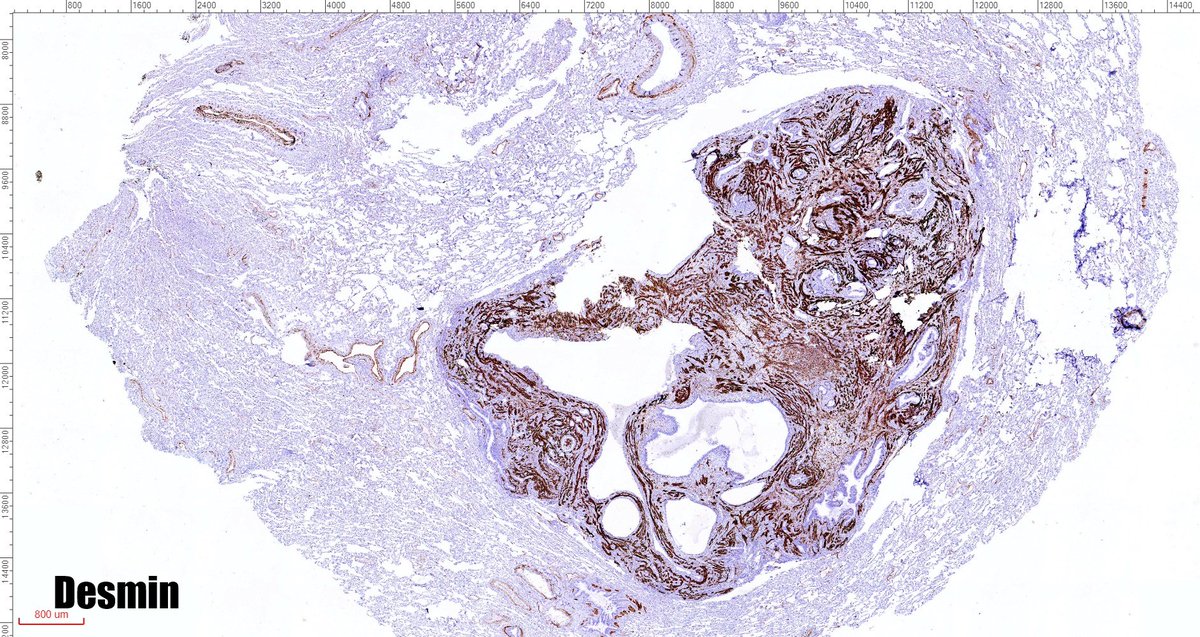

One of the most cryptic lesions for me in #pulmonarypath is the so called benign metastasizing leiomyoma. This case is a 37yo after myomectomy 3 years ago.

fabiotavora's tweet image. One of the most cryptic lesions for me in #pulmonarypath is the so called benign metastasizing leiomyoma. This case is a 37yo after myomectomy 3 years ago.